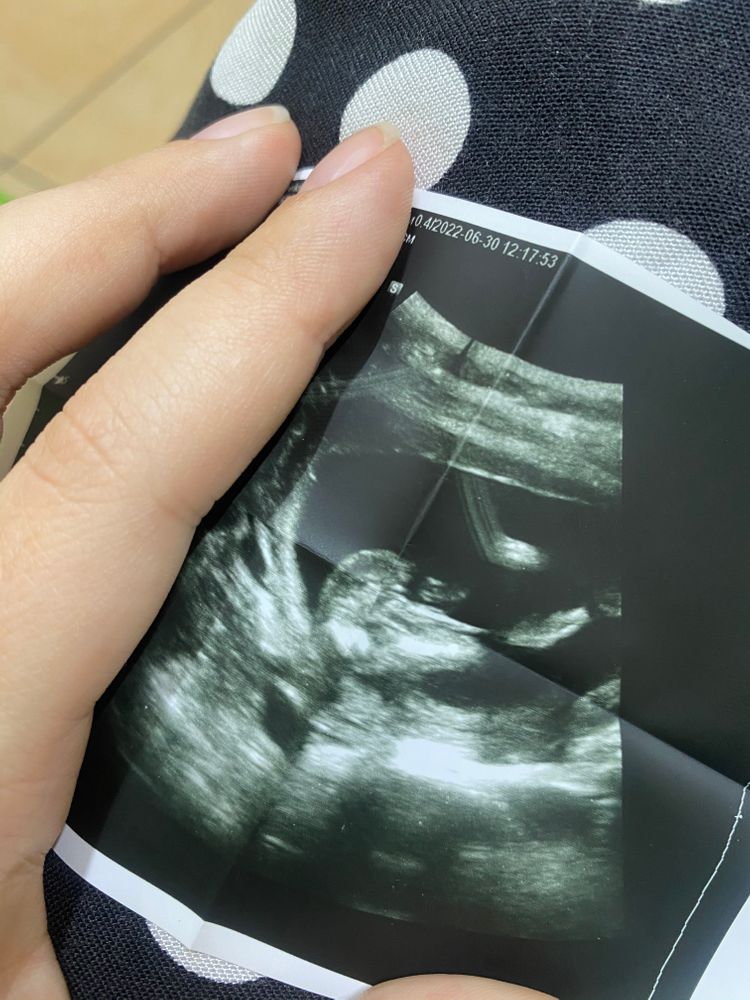

Мальчик или девочка ?

Вообще не пойму где что на вашем снимке)

Mama Sveta, Изображение Вот стрелочкой навела на самое интересное

Элина, если мне зрение не изменяет😁 то я отчётливо вижу женские гениталии , две белые полосочки это и есть ПГ девочки , я уже третью жду, и УЗИ прошла вдоль и поперек, оставлю 5% на мальчика, а 95 девочка

девочка похоже,полосочки )) то что там торчит пуповина наверное

Счастье есть , узист говорит вроде бы на девочку похоже, но тоже сомневается

Вижу девочку, а сверху возможно просто пуповина

Девочка 🌸🌸🌸